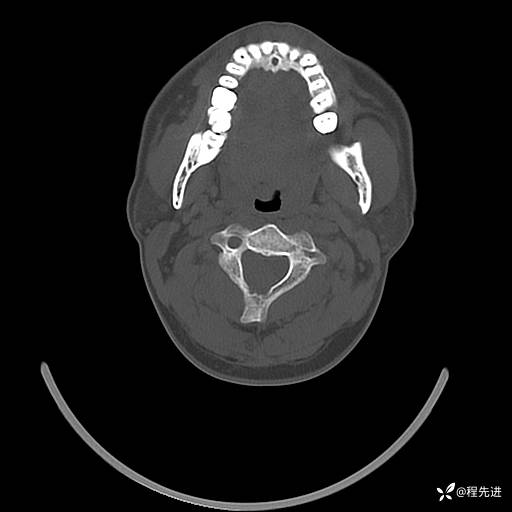

CT平扫+增强: